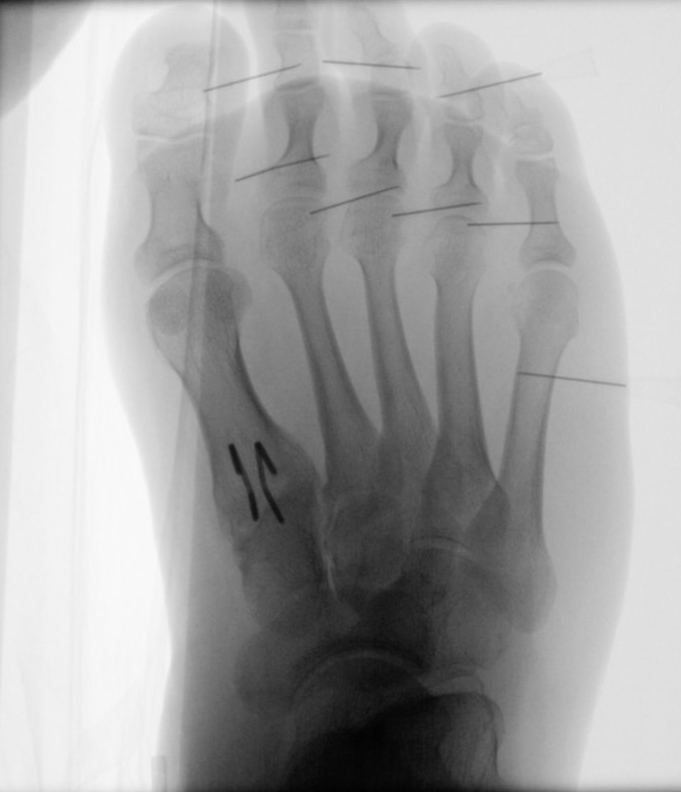

In der minimalinvasiven Fußchirurgie ist es unabdingbar, die Fräse in ihrer Position zum Knochen radiologisch zu kontrollieren, damit vulnerable Wachstumsfugen oder angrenzende Gelenke nicht verletzt werden. Zu diesem Zweck werden mit einem Bildwandler während der Operation die genaue Position der Fräse und der Osteotomieverlauf überprüft, was die Strahlenbelastung im Vergleich zu offenen Verfahren erhöht. Diese Strahlenbelastung hat potenziell einen schädigenden Einfluss auf den noch blutbildenden Knochen von Heranwachsenden. Gesicherte Landmarken am Fuß können die notwendige Zahl der Röntgenbilder und damit die Strahlung minimieren. Ist es erforderlich, mehrere Knochen zu osteotomieren, wie zum Beispiel im Bereich der Kleinzehen, werden anhand der Landmarken kleine Injektionsnadeln auf Höhe der geplanten Osteotomien vorgelegt und radiologisch im Bildwandler (BV) dokumentiert (Abb. 11). Ein solches Bild schafft eine gute Orientierung, sodass auf radiologische Kontrollen intraoperativ weitestgehend verzichtet werden kann.

Abb. 11: Lokalisation mehrerer Stichinzisionen mit einem Röntgenbild.

Zum Lesen der Bildbeschreibung und zur Vollansicht bitte das Bild anklicken. Bild: A. Helmers.